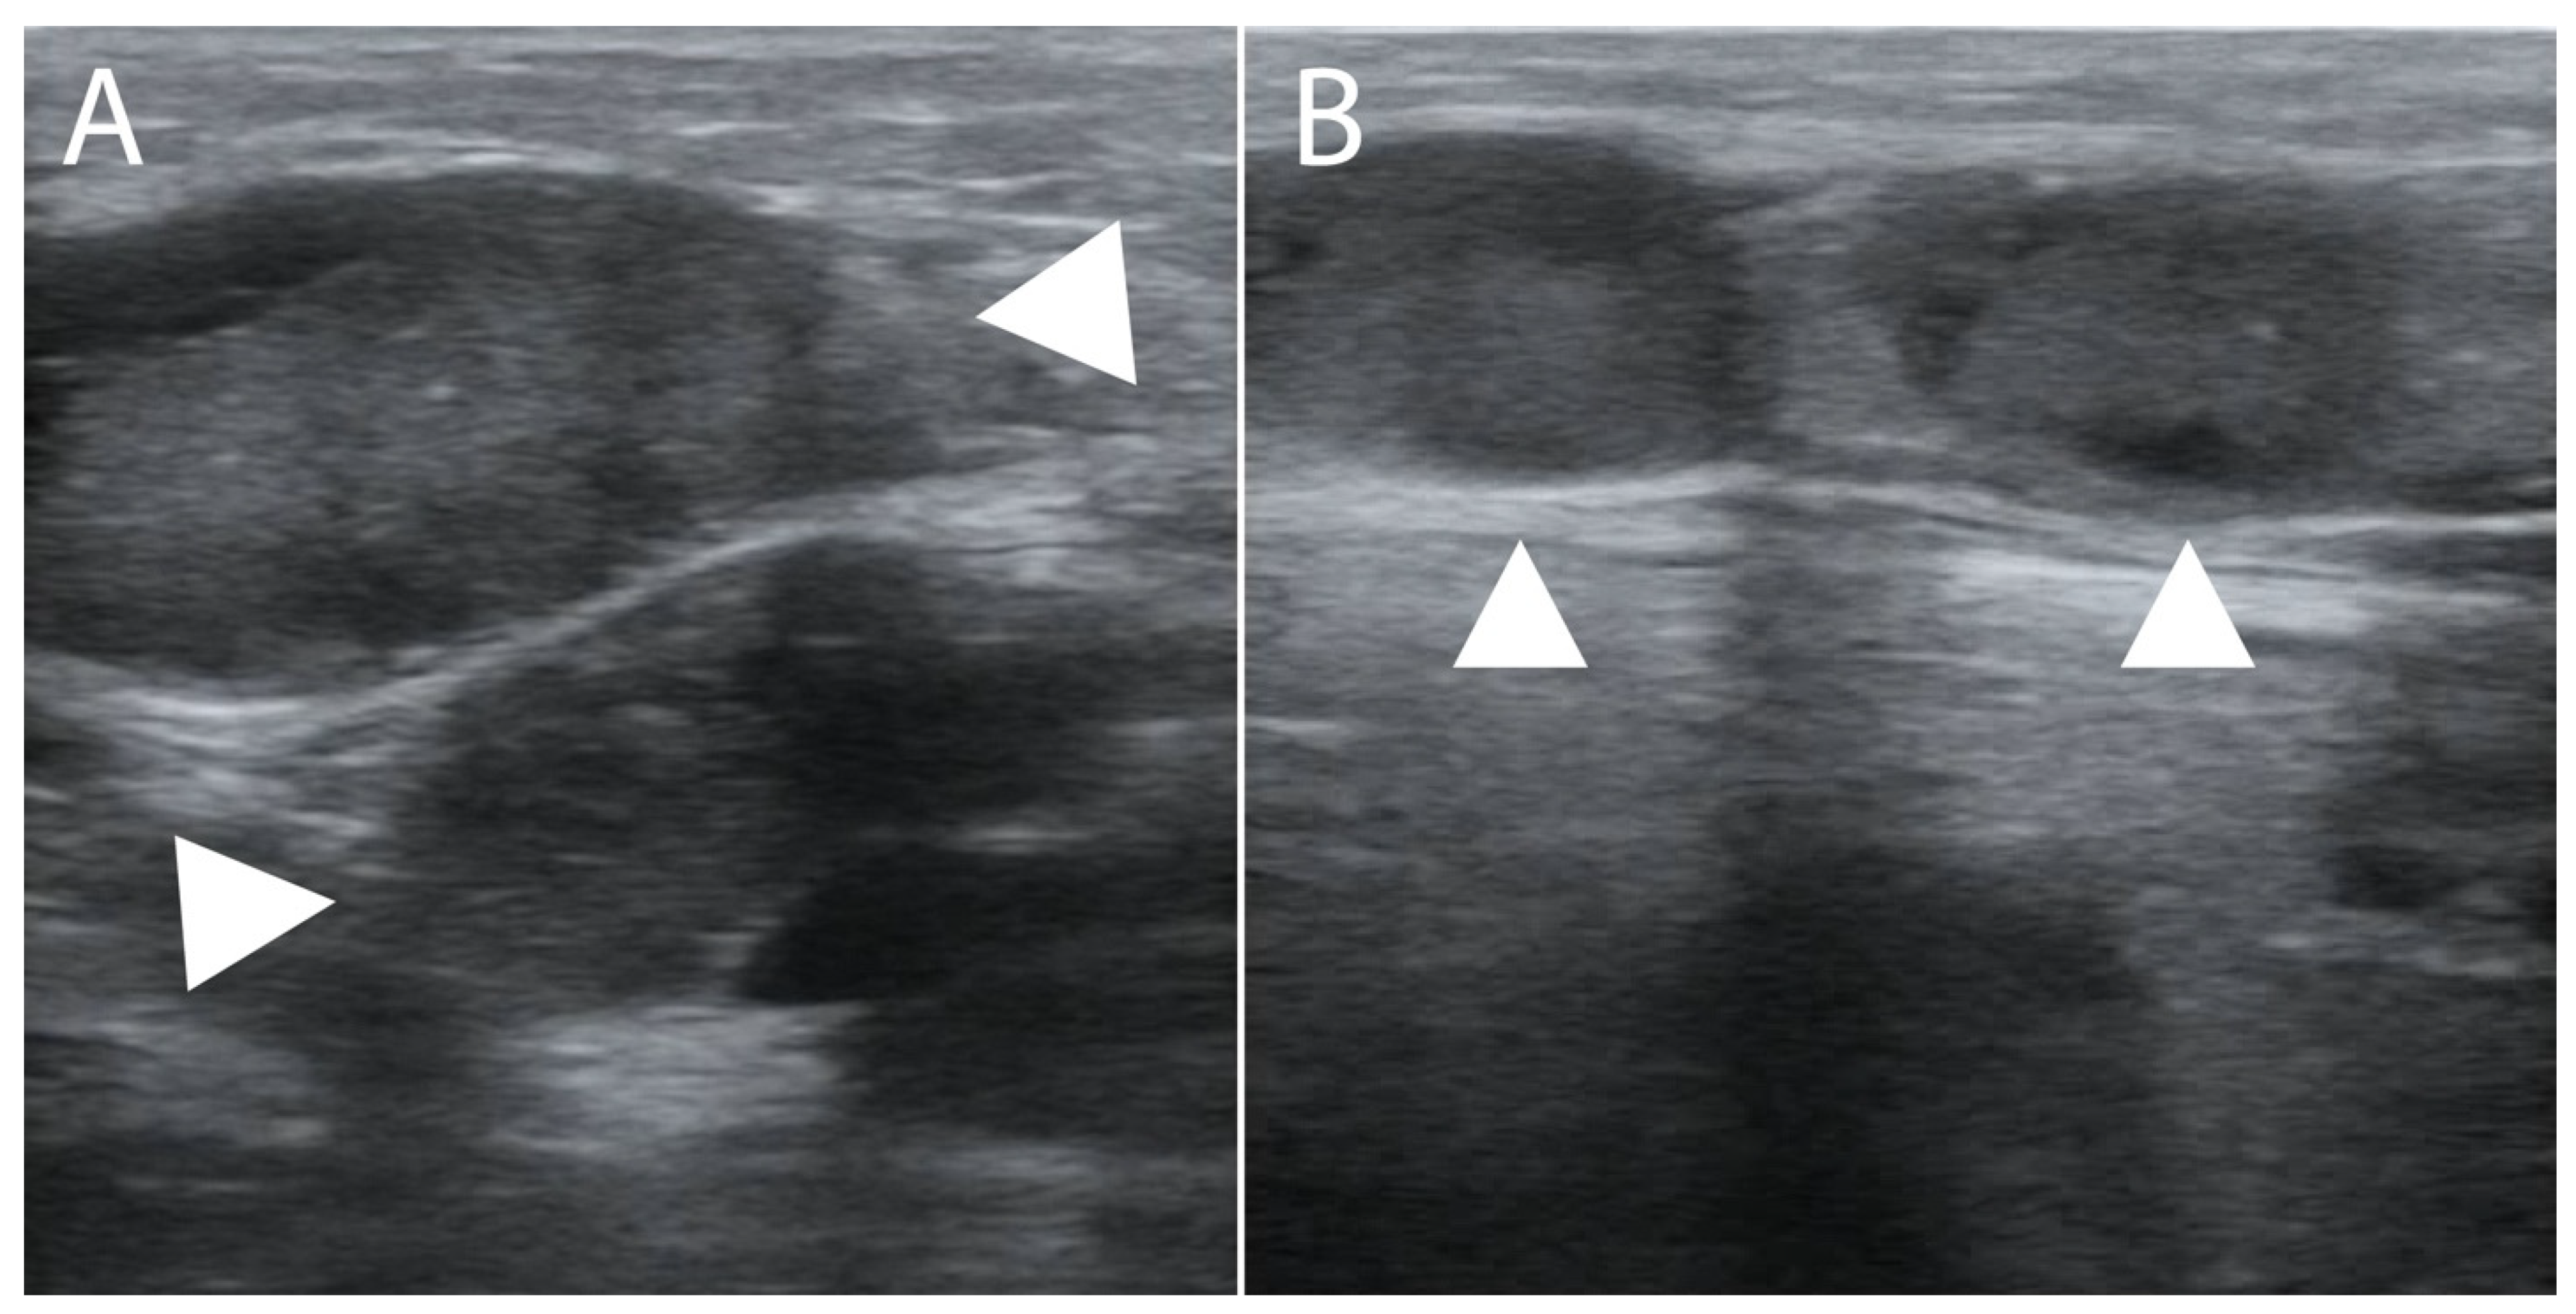

| Day 2 | Ultrasound revealed bilateral pleural effusions, pelvic free fluid, and hyperechoic splenic lesions consistent with disseminated KS. Right thoracentesis removed 1300 mL blood-stained fluid. Received first cycle of IV paclitaxel 100 mg/m2, IV dexamethasone 12 mg, third dose of ceftriaxone 2 g. |

- Huson, M.A.M.; Kumwenda, T.; Gumulira, J.; Rambiki, E.; Wallrauch, C.; Heller, T. Ultrasound findings in Kaposi sarcoma patients: Overlapping sonographic features with disseminated tuberculosis. Ultrasound J. 2023, 15, 27. [Google Scholar] [CrossRef] [PubMed]